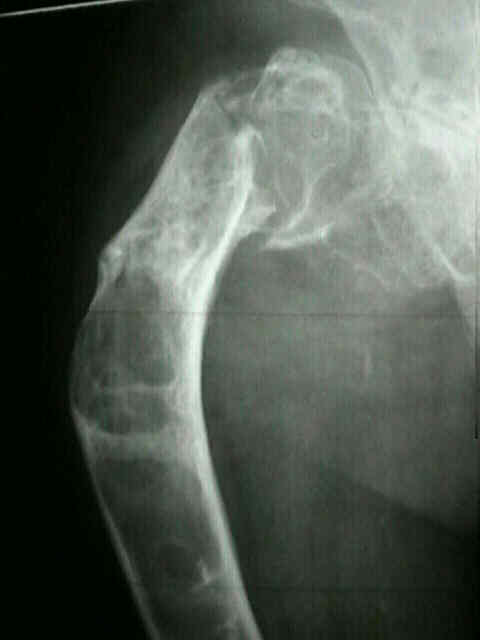

La radiografía simple es la prueba inicial y la más importante. Muestra una lesión intramedular expansiva con adelgazamiento cortical y un patrón característico de “vidrio esmerilado” (ground-glass) o nebuloso, producido por la mezcla de hueso inmaduro y tejido fibroso. En el fémur proximal puede observarse una tendencia a la deformidad en varus (“cayado de pastor”).

- Deformidad progresiva – coxa vara en el fémur (“cayado de pastor”), deformidad en antecurvatum en la tibia.